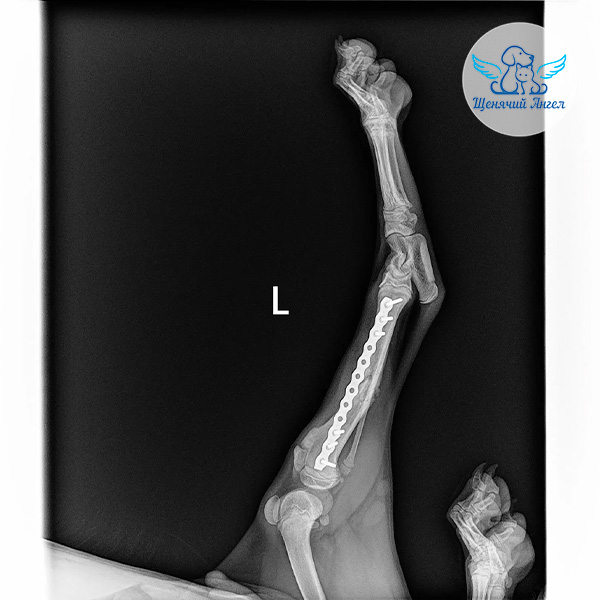

🩻 Рентген показал перелом голени левой задней лапы. Кроме того, на фоне травмы у Джоя открылось кровотечение в желудочно-кишечном тракте. К счастью, его удалось остановить медикаментозно.

После проведения необходимых обследований Джою выполнили операцию – остеосинтез на повреждённой лапе.

Во время хирургического вмешательства врачи зафиксировали перелом с помощью специальных металлических конструкций, чтобы кость могла правильно срастись 🐾